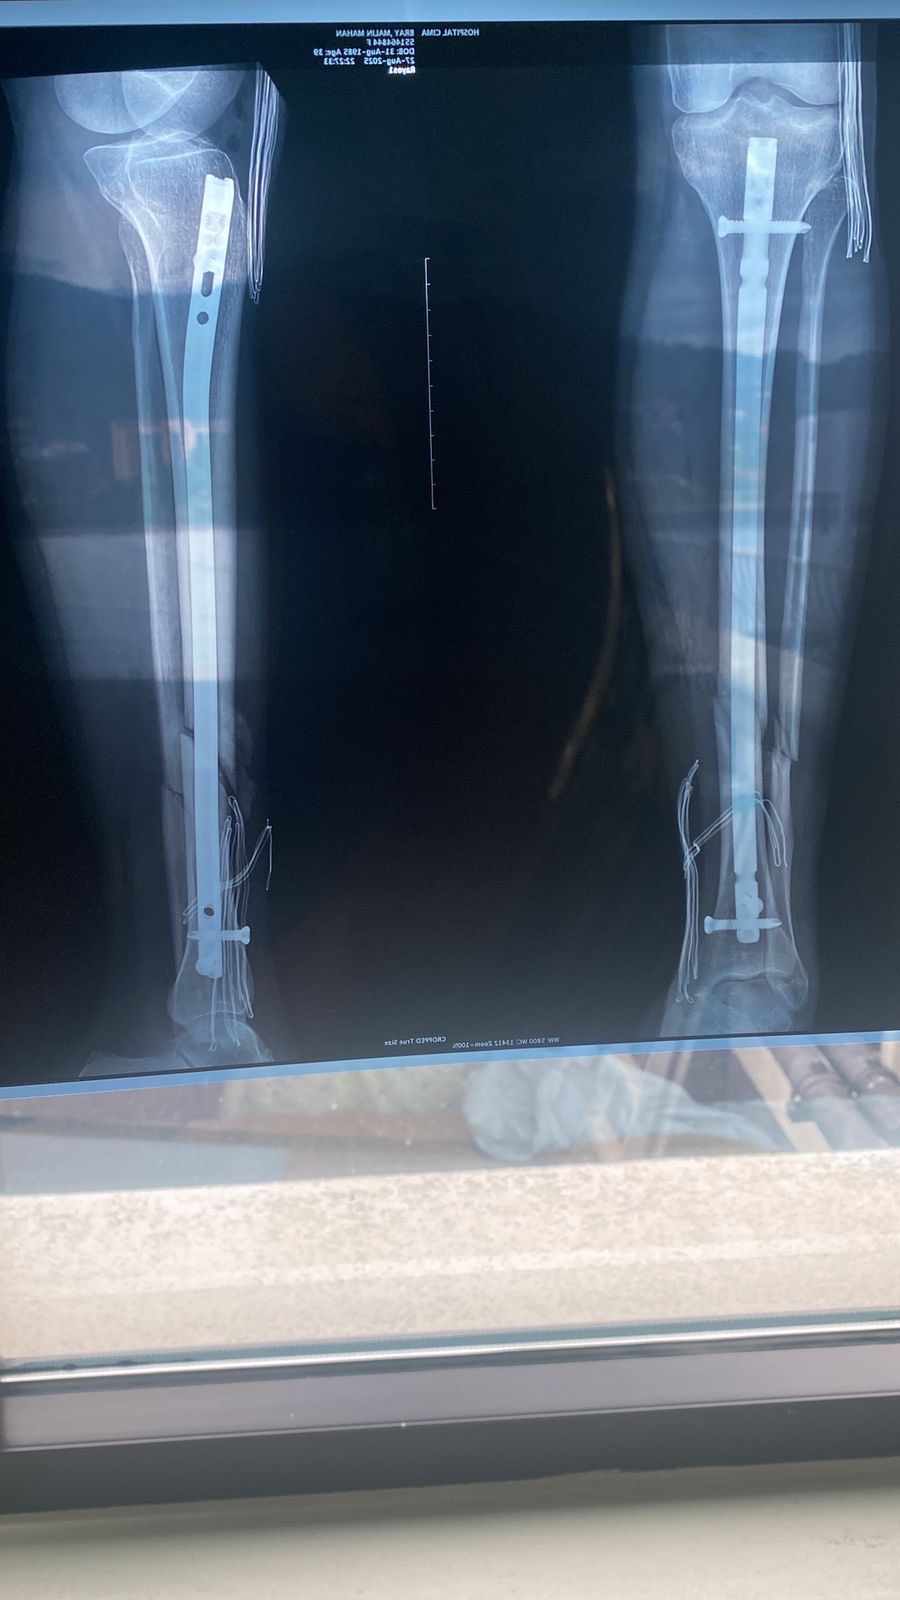

We’re so relieved and grateful to share that Malin’s surgery went well and she’s now beginning the healing process. The procedure was successful, and she’s currently resting and recovering.

While this is a major step forward, Malin still needs help covering the full cost of the surgery, hospital stay, and the months of recovery ahead. She’ll also need physical therapy multiple times a week, which is essential for her to fully regain strength and mobility in her leg.